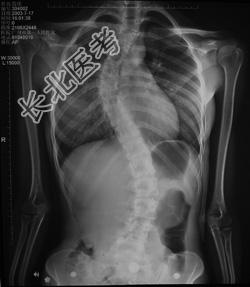

- [材料题] 病历摘要: 患者××,女,17岁,发现剃刀背畸形3个月。查体:脊柱胸段向右侧凸,腰段向左侧凸,右胸廓呈剃刀背畸形,双下肢未见明显异常。

- 多项选择题2.该患者的诊断是: 提示: 患者 X线片见图:

A、特发性脊柱侧弯

B、麻痹性脊柱侧弯

C、先天性脊柱侧弯

D、神经肌肉性侧弯

E、神经纤维瘤病

F、外伤性侧弯